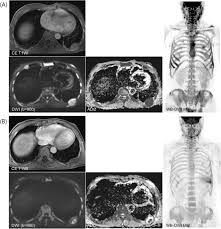

The Use Of Whole Body Mri In Multiple Myeloma Rcp Journals

The Use Of Whole Body Mri In Multiple Myeloma Rcp Journals from www.rcpjournals.org

Multiple myeloma is a cancer of plasma cells, which are white blood cells found mainly in the bone marrow. Find more information on clinical trials that are open for enrollment at mount sinai's center for excellence for multiple myeloma. Multiple myeloma (mm), also known as plasma cell myeloma and simply myeloma, is a cancer of plasma cells, a type of white blood cell that normally produces antibodies. Treatment response, detection of relapse. Related online courses on physioplus. 16,000 new cases and 11,000 deaths. Changing the treatment landscape for hematologic malignancies learn more. In multiple myeloma, when the cancer protein level is up, the normal antibody levels are down. If you still can't find it, please let us know so we can add it!. Tell the radiologist or the radiology technician about your diagnosis before receiving dye injection into. It accounts for approximately 10% of all. Other tests include blood monoclonal immunoglobulin and radiology tests to determine the extent of bone lesions. Spotlight revised international staging system for multiple myeloma: